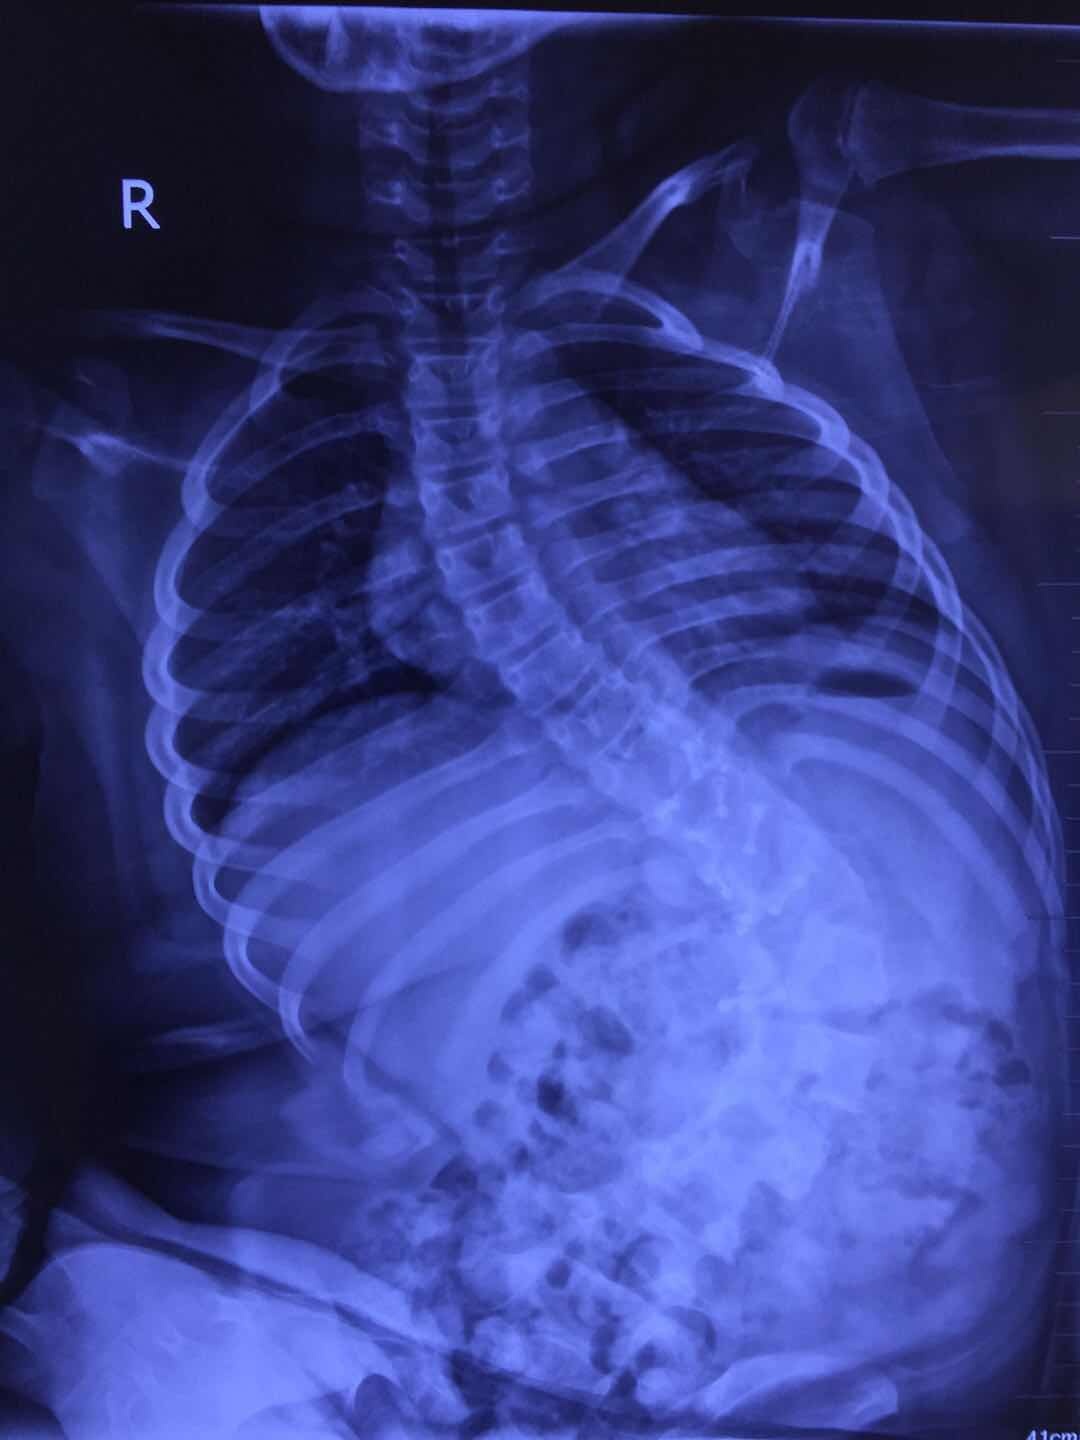

郭晓东提供的影像学资料显示,下腰瘫痪后的孩子脊柱弯成了这样。